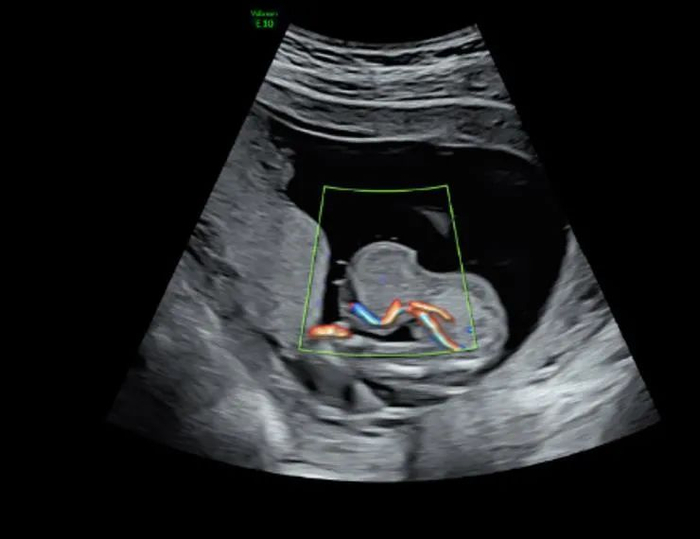

去年9月,黄女士历尽艰辛终于怀孕了。在她憧憬成为母亲的美好未来之时,超声筛查的结果却给了她当头一棒:III级超声检查结果显示,胎儿脐膨出,突出物大小35毫米×36毫米×36毫米

脐带腹部入口处低回声包块,13毫米×12毫米×12毫米,考虑胎儿脐膨出声像。

超声检查结果显示胎儿“脐膨出”,且内容物为肝脏,虽然膨出不算非常罕见的先天性畸形,但是如果肝脏跑出来了,就有可能是腹裂了,预后会差很多。

高羽主任的一番话给了黄女士信心,她选择继续在中山六院产检。孕27周时,超声显示,宝宝其他方面发育良好,但脐膨出的大小已经达到45毫米×46毫米×44毫米(约为成年人拳头大)。